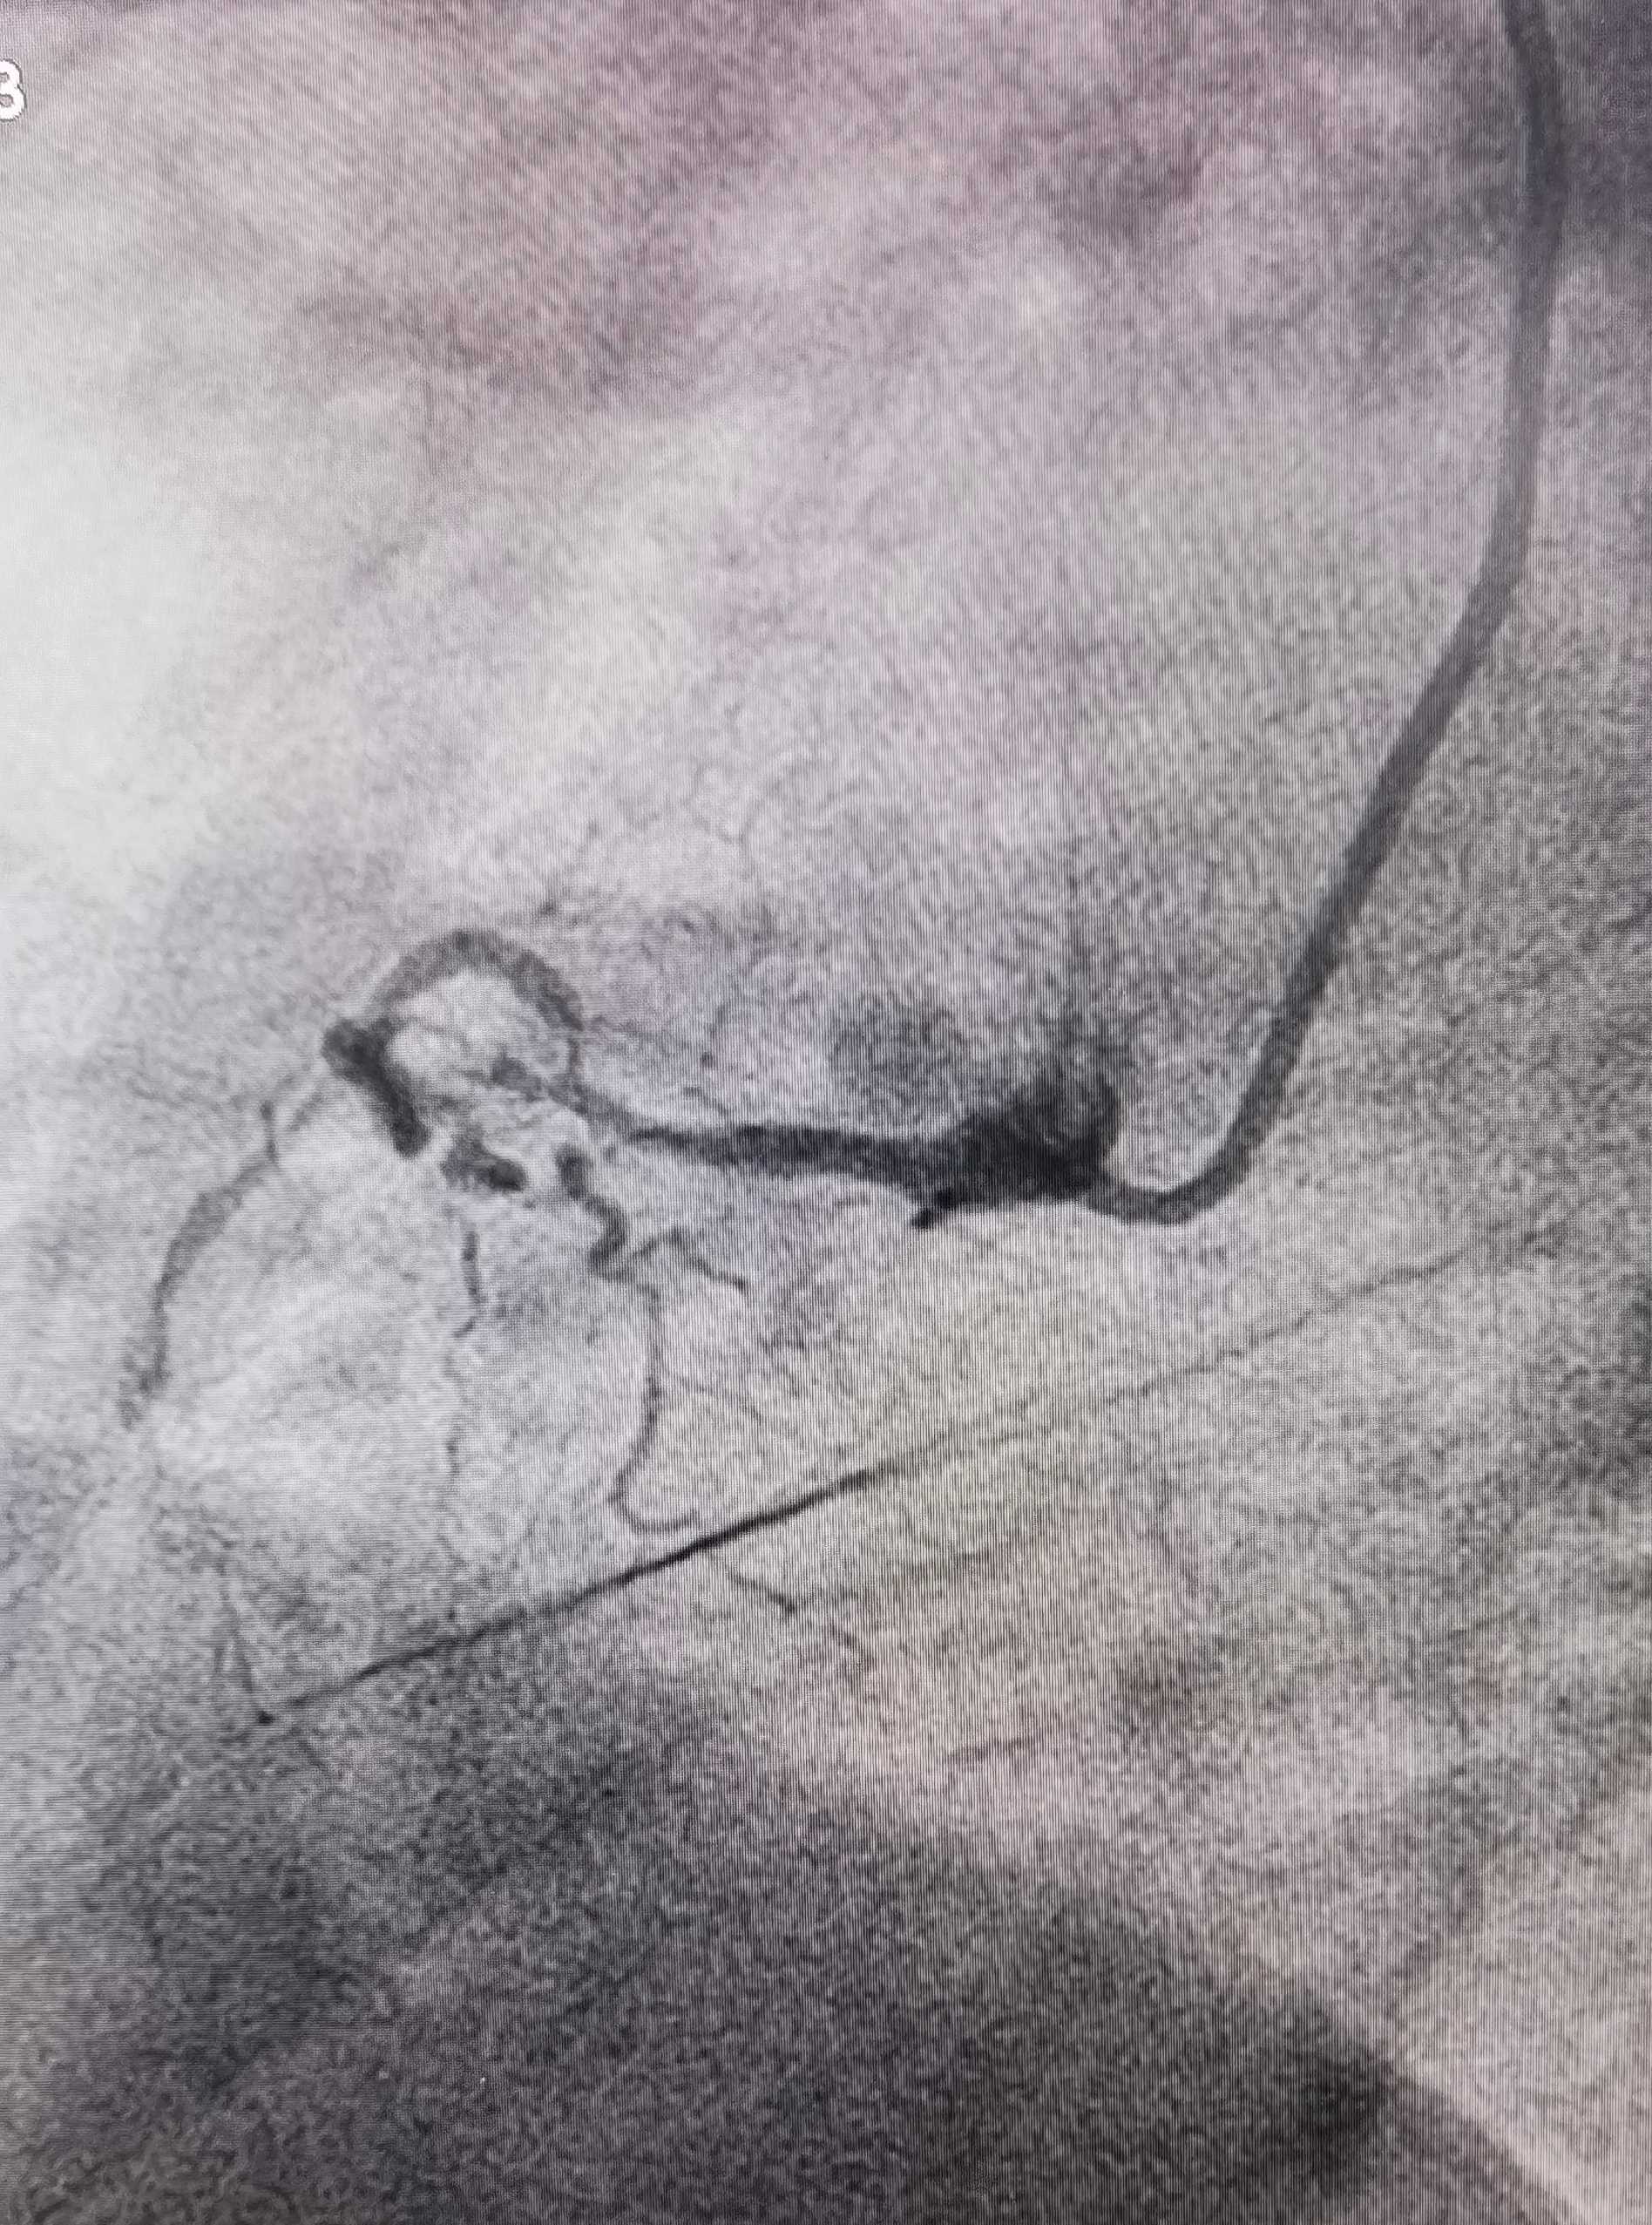

“时间就是心肌,时间就是生命”必须尽快为患者打通堵塞的血管。然而,进一步的冠状动脉造影结果让接诊的心血管内一科副主任李鹏博士心头一震:张大叔的血管情况十分复杂,心脏的三支主要血管均有严重病变:左前降支(LAD)全程斑块浸润,近段狭窄90%;左回旋支(LCX)全程斑块浸润,远段狭窄80-85%,第二钝缘支(OM2)细长口部狭窄90%;右冠状动脉(RCA)近段及远段完全闭塞。

术前LCX

在心血管内一科主任郎九立的指导下,副主任李鹏、医师王耀萱与巡回护士马海波等迅速组成救治小组。他们面临巨大挑战:需要在完全闭塞的血管中,用比头发丝还细的导丝寻找到真腔,重建血流。凭借丰富的经验和娴熟的手法,团队在患者最危险的右冠状动脉(RCA)病变处顺利完成介入治疗,精准植入支架并应用药物球囊。术后患者胸痛、气短症状完全消失,生命体征平稳。后续将择期对左前降支(LAD)、左回旋支(LCX)病变进行介入治疗。